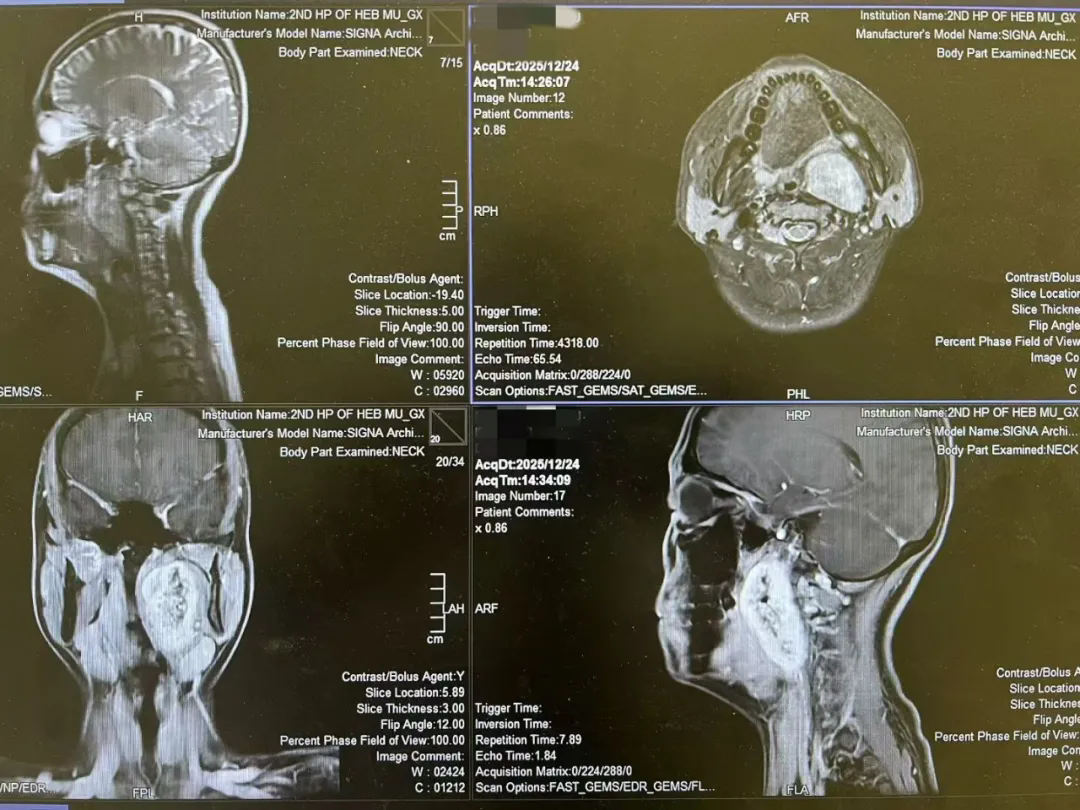

医者心声 | 这份信任,重如千钧!

一台经口入路咽旁间隙巨大肿物切除术后的随笔 今天,完成了一台有些特别的手术。 患者是一位年轻的女孩,咽旁间隙,七厘米的巨大肿物。像一颗沉默的炸弹,深藏在颈侧的重重屏障之后——...